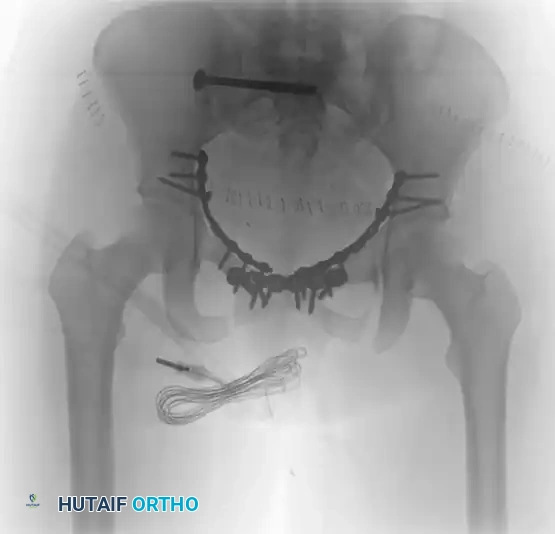

The following radiographic series demonstrates the successful transition to definitive internal fixation in a vertically unstable pelvic fracture, utilizing an anterior symphyseal plate and a posterior sacroiliac screw:

TREATMENT Surgical Diagram

Postoperative Inlet view. This projection critically evaluates the anterior-to-posterior translation of the pelvic ring and confirms that the sacroiliac screw is safely contained within the sacral vertebral body, avoiding the spinal canal anteriorly.